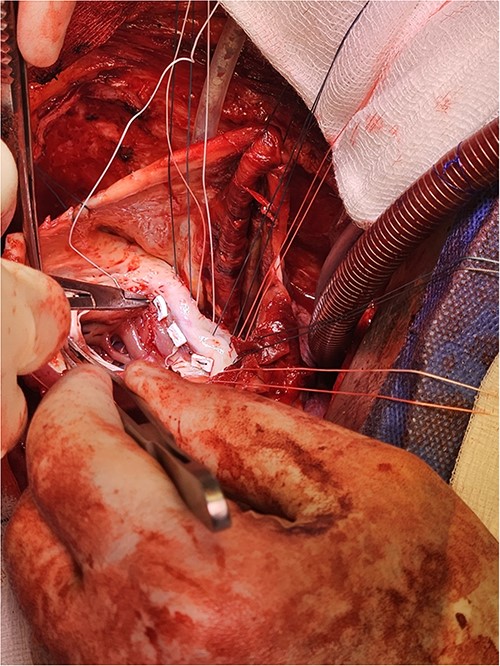

Following median sternotomy, cardiopulmonary bypass was instituted (bicaval drainage, ascending aortic return). Antegrade cardioplegia was delivered with aortic root venting and bicaval snaring. Dense adhesions surrounded the aneurysm, which had a thin wall, measured ⁓15 cm from LV apex to mitral annulus, and contained around 150 g of clot. The posterior mitral leaflet appeared retracted, preventing coaptation due to LV stretching. The aneurysm was resected (Fig. 2), and the LV wall repaired with a 5 × 3 cm patch, restoring normal LV size (Fig. 3). The musculotendinous junctions of the anterior and posterior papillary muscles were approximated using pledgeted 3–0 polypropylene sutures (Fig. 4). The patch repair was completed (Fig. 5), and the overlying sac oversewn for haemostasis.

Pledgeted Ethibond sutures were placed circumferentially around the aneurysm mouth.